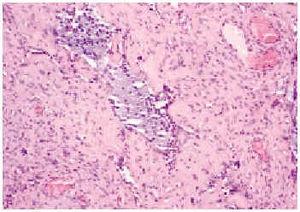

En el estudio histopatológico de la pieza se observó una lesión tumoral mal delimitada que ocupaba prácticamente toda la dermis (fig. 2) y que se extendía hacia el tejido celular subcutáneo. El tumor estaba constituido por células fusiformes y ovales, otras grandes de núcleos pleomórficos y células gigantes multinucleadas, en una estroma hialina (fig. 3). Se observaban además hendiduras, delimitadas por células grandes de núcleos hipercromáticos y células gigantes multinucleadas, que en su interior contenían células necróticas flotando en una sustancia basófila (fig. 4).

Fig. 3.--Se aprecian células de núcleos hipercromáticos en una estroma hialina, y seudoluces vasculares o «espacios angiectoides» con células necróticas en su interior (hematoxilina-eosina, ×20).